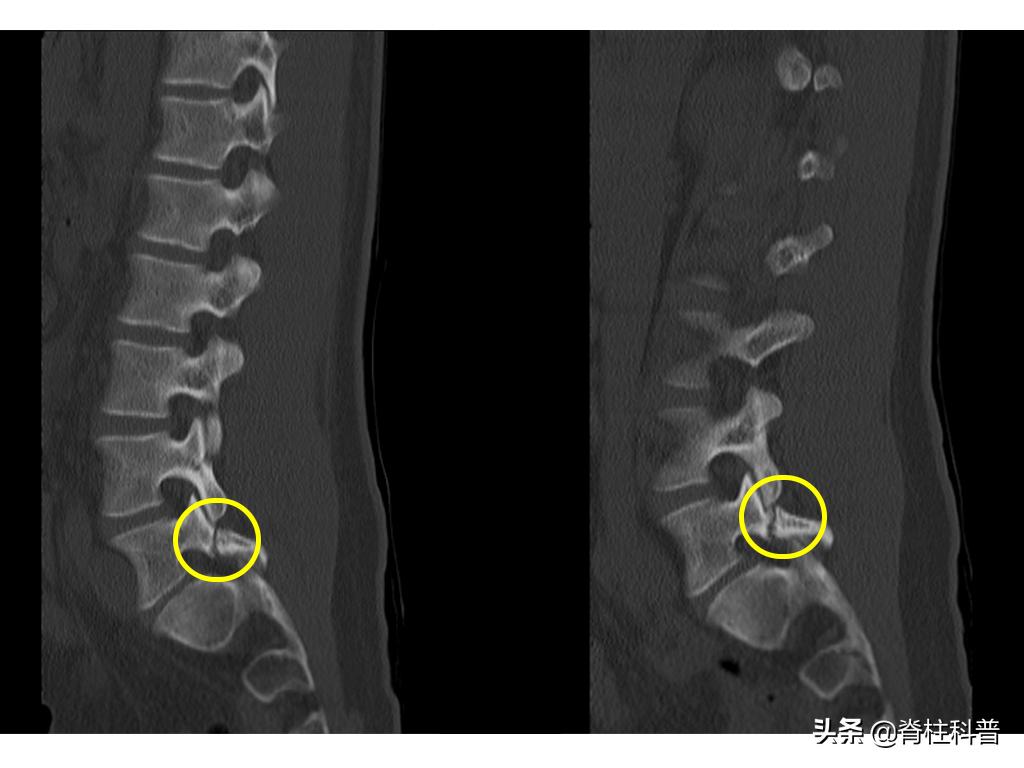

腰椎峡部裂是指椎弓崩裂,或者是峡部不连,主要指腰椎椎弓上关节突与下关节突间出现骨质缺损的情况,且呈不连续特征。看不懂?没关系,我用腰椎CT告诉你,请仔细看下图:

峡部裂断裂处